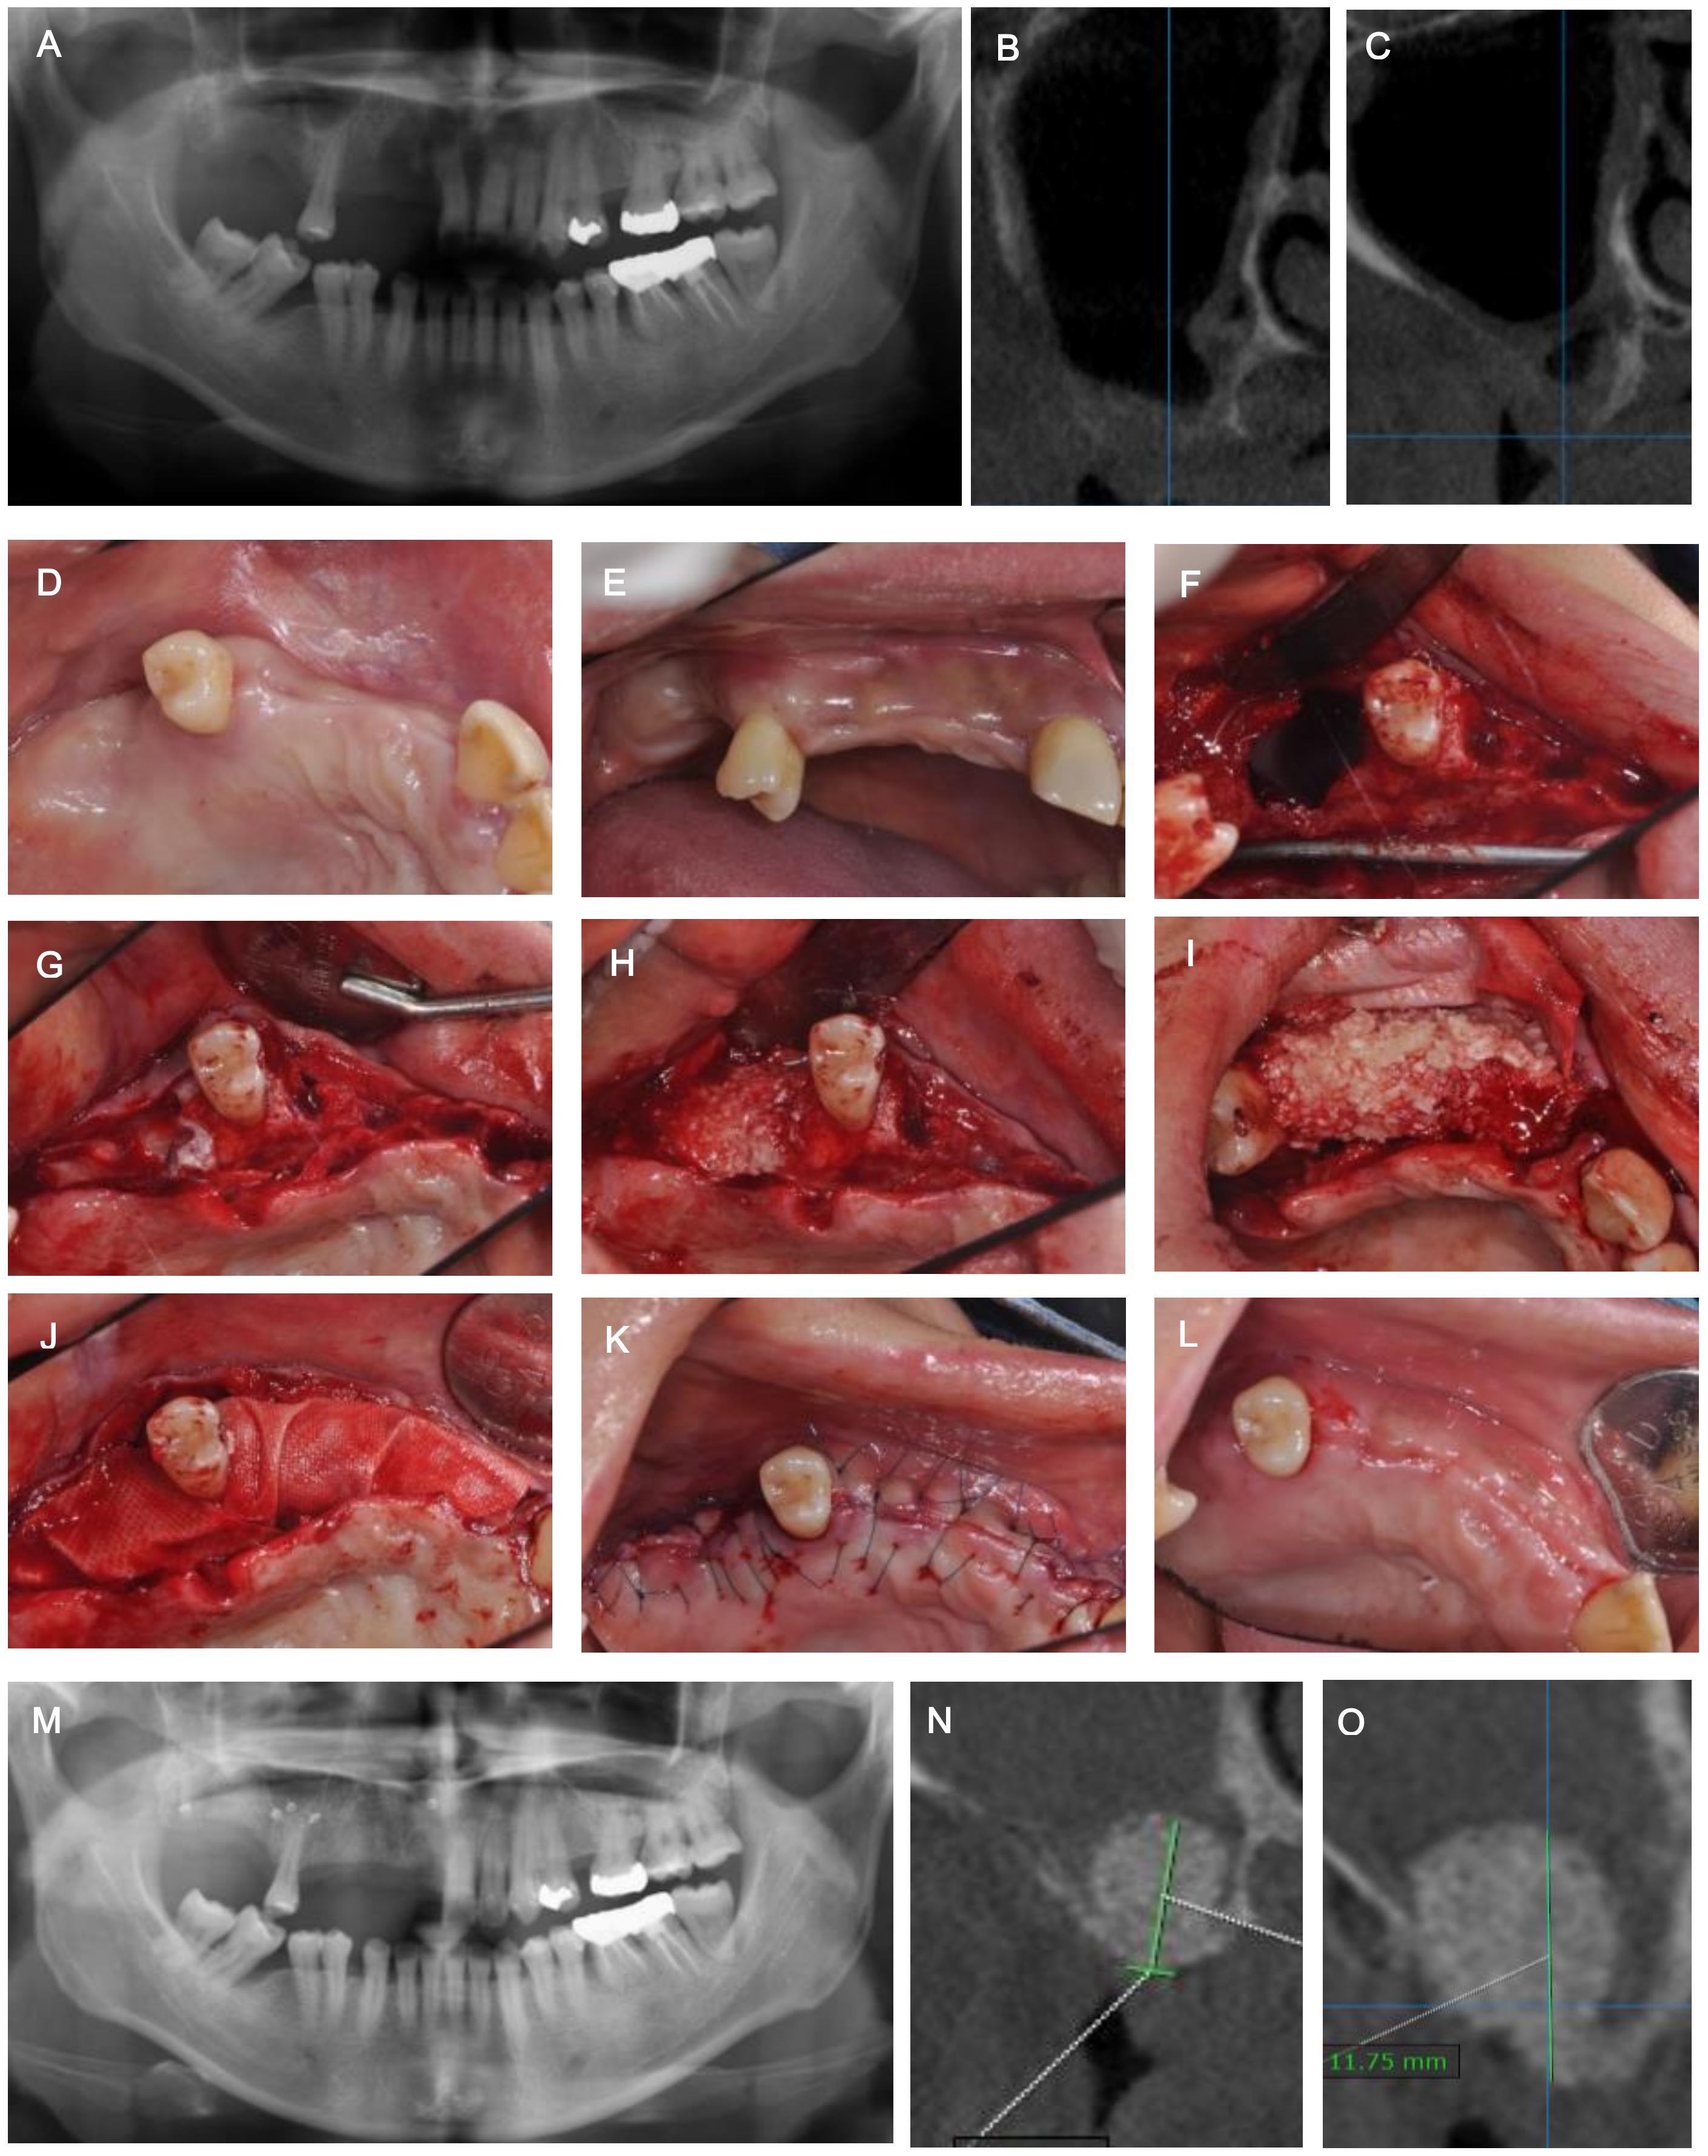

2. Case Description